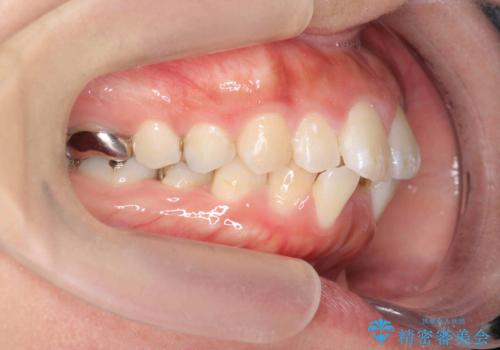

前歯の角度を改善するマウスピース矯正

- 前歯の角度・重なりの改善を求めて矯正治療を希望され来院されました。

通常このような場合、小臼歯を4本抜去しワイヤー矯正を行う治療計画も検討されますが、今回は側方に拡大できる骨量が十分に存在したため抜歯をしない矯正治療の計画を立てます。

しっかりと拡大を行い、IPRも併用したことで歯並びと前歯の角度を大幅に改善することができました。